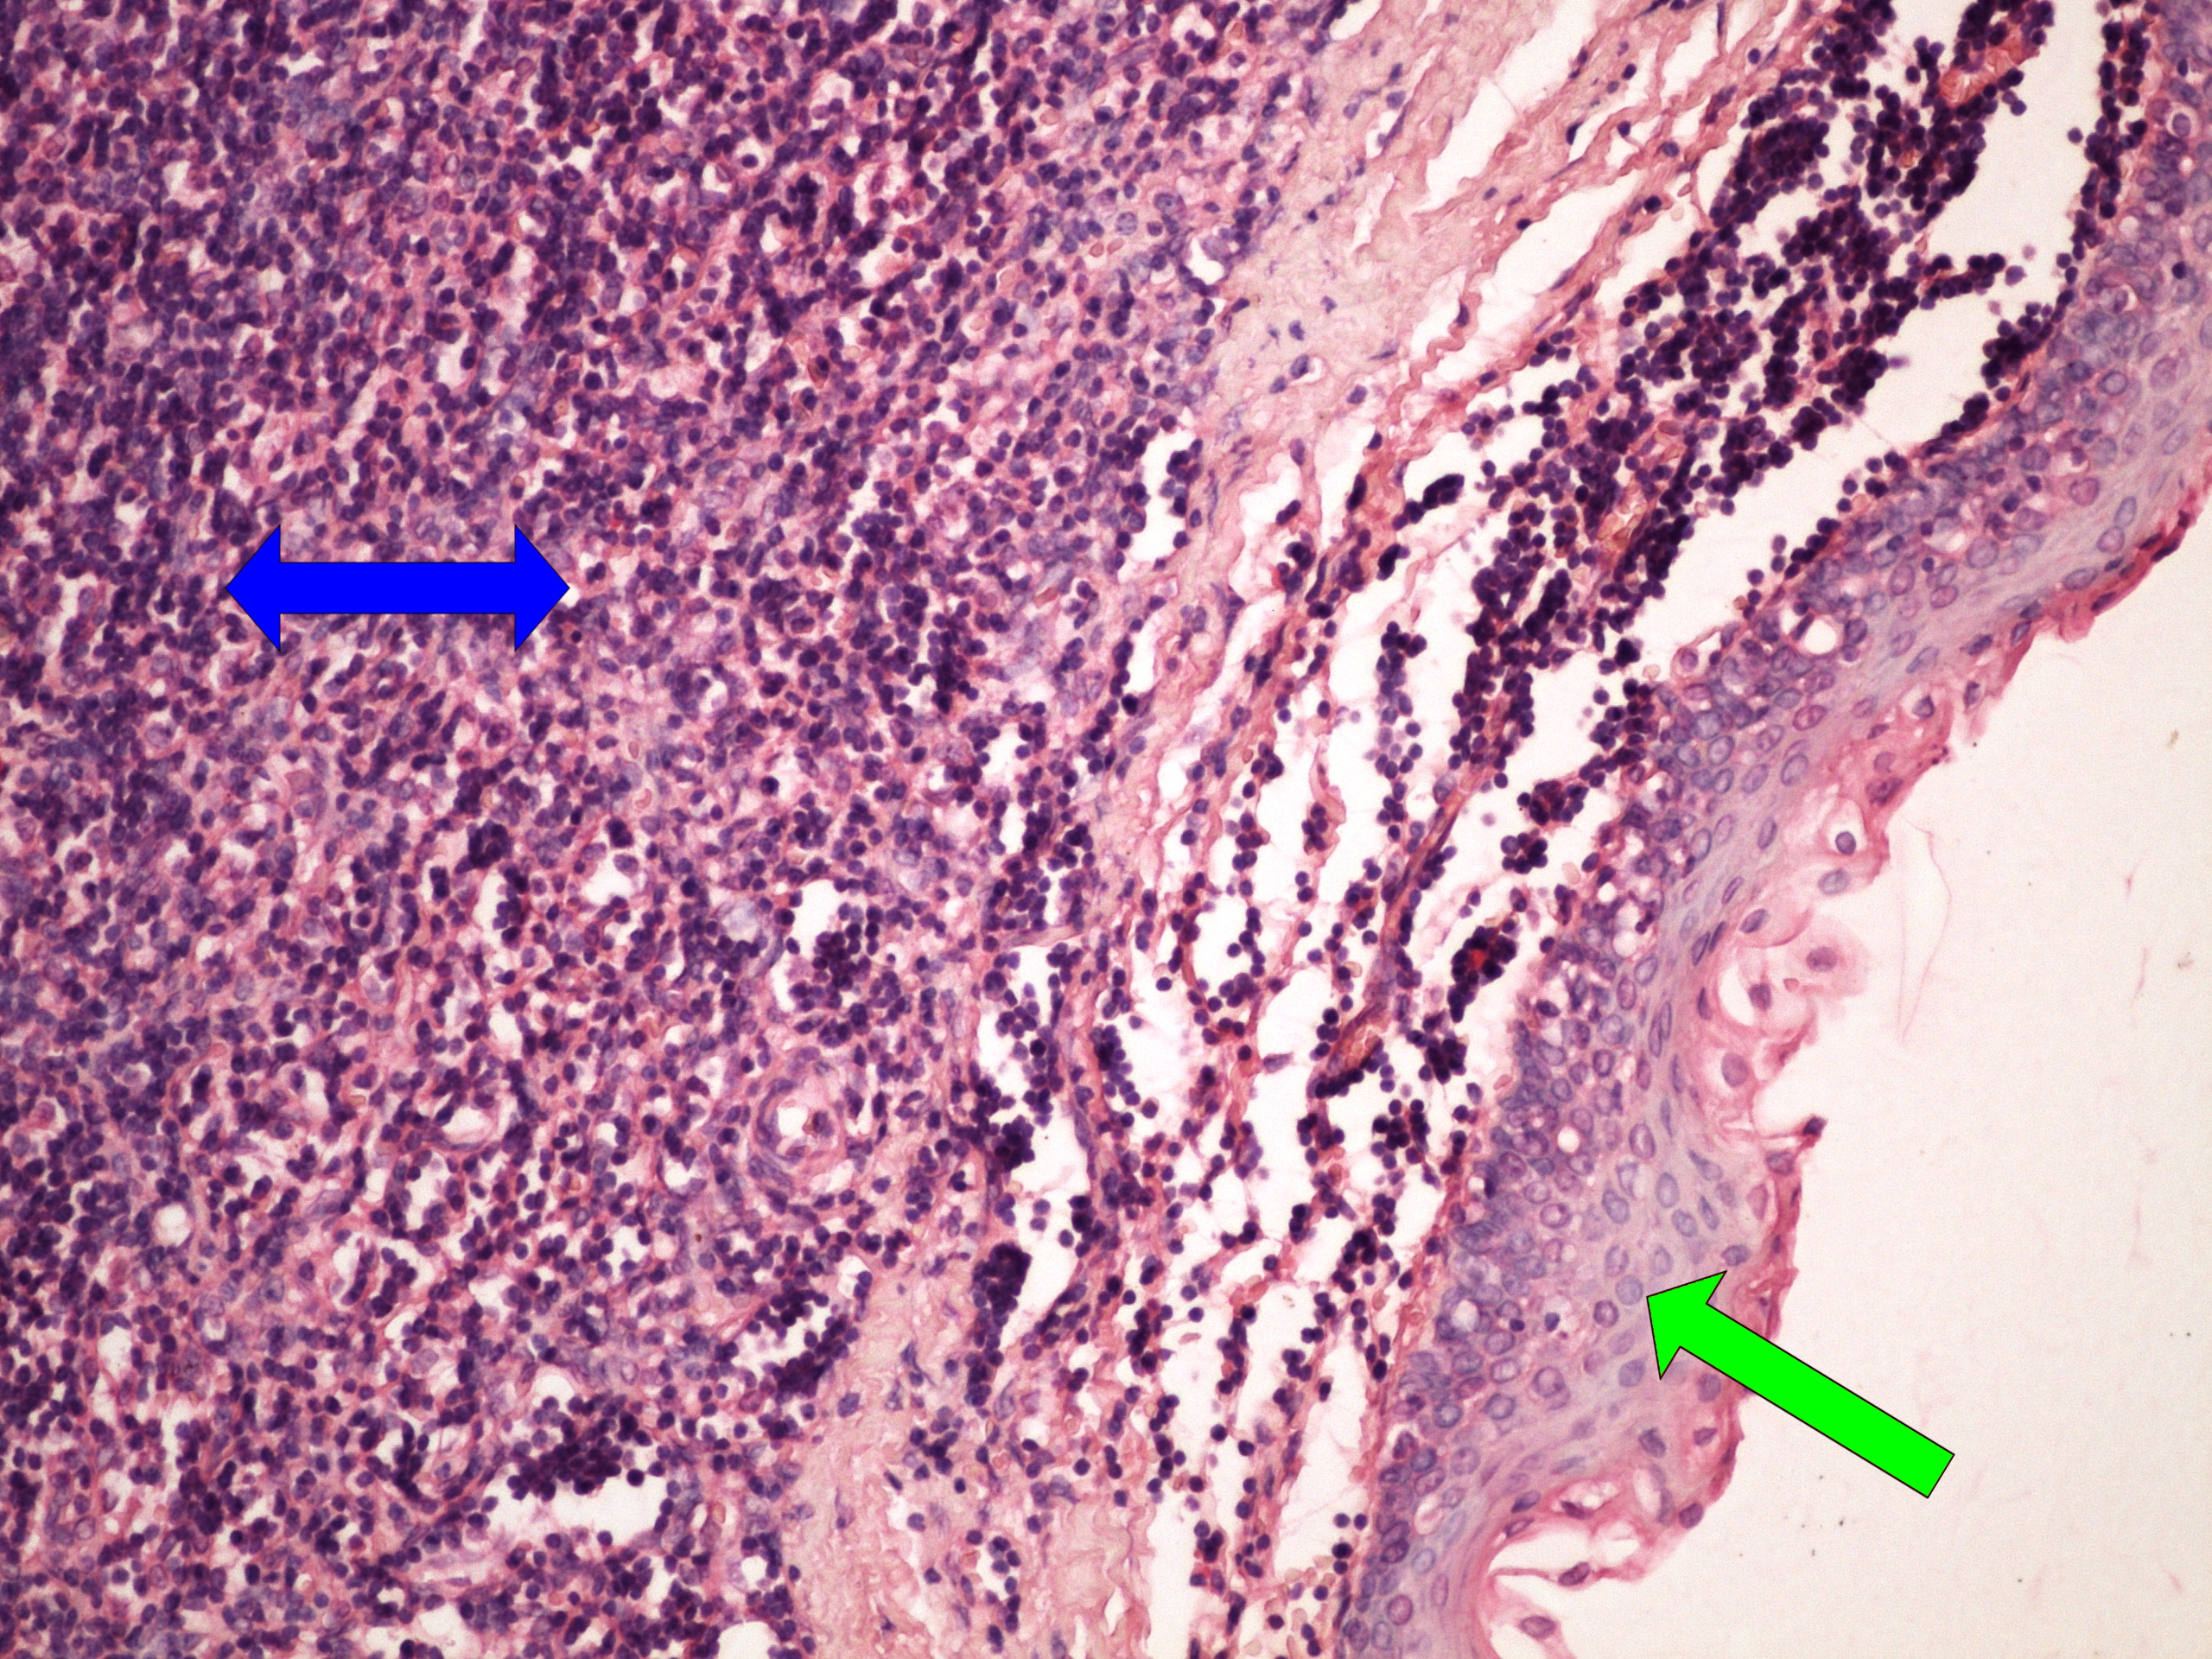

Preparát č.13 a č.14 - CIN

Struktury

- žlázka

- ložiska CIN bez invaze

- zánětlivé ložisko

- atypie v celé šíri epitelu